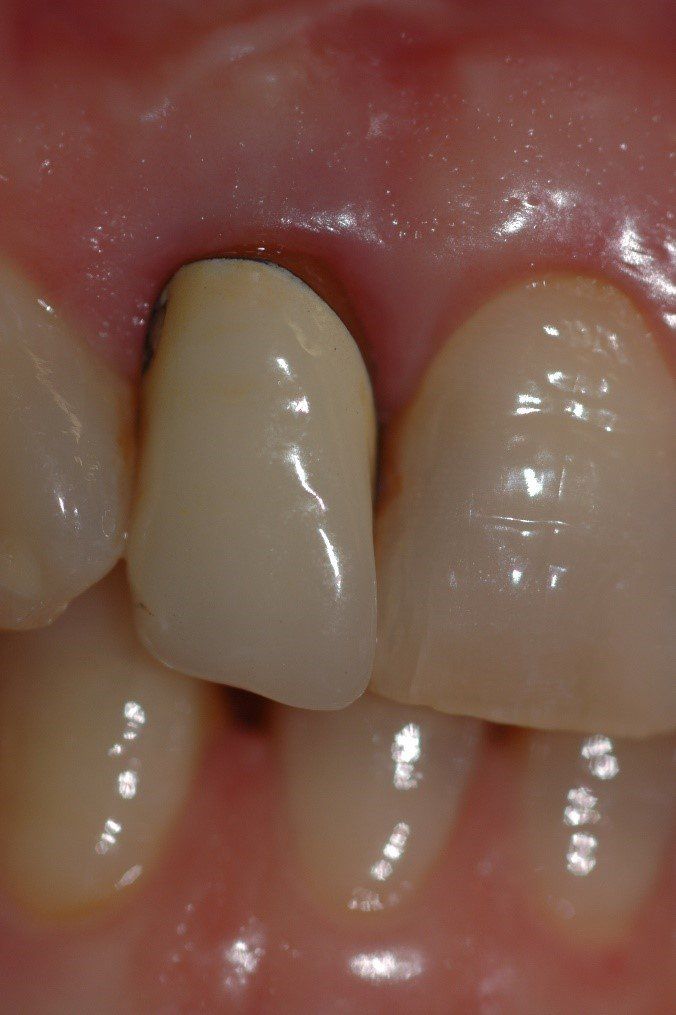

Visione clinica del Maryland bridge cementato con tecnica adesiva ed immagine tomografica tridimensionale per valutare lo spessore bucco palatale utile all’inserimento dell’impianto che fu valutato come sufficiente benchè esiguo. A tal proposito deve essere sottolineato che la letteratura consiglia, quando è disponibile un volume di osso residuo utile all’inserimento di un impianto, di evitare tecniche di innesto osseo in quanto un aumento dei volumi ossei non migliora la prognosi estetica (3)